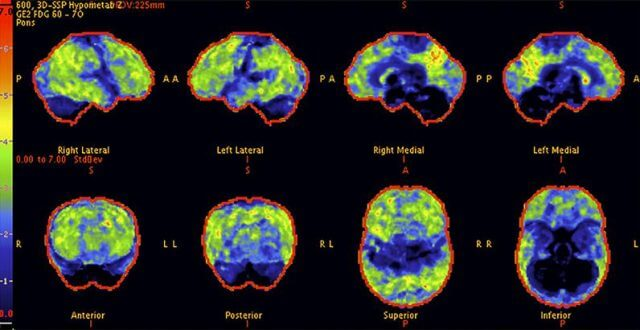

Above: A 68-year-old woman with a 10-year history of cognitive issues. Previous PET scans showed significant metabolic decline.

Above: The patient’s PET scan after AlzClipp treatment shows improvement, with cognitive abilities greatly enhanced as the scan approaches that of a normal brain.